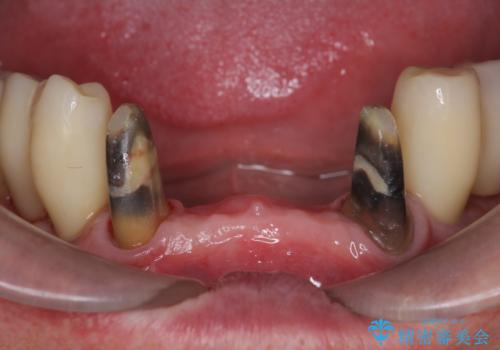

- 被せてある前歯がぐらぐらする、口臭も気になるし、常に歯ぐきが腫れていていることの改善をして欲しい、と来院されました。

歯周組織検査・X線写真検査の結果、重度歯周病であることがわかりました。

残すことのできない歯を抜去し、入れ歯になることを回避すべくブリッジ治療を行いますが支台となる歯の歯周病を改善すべく歯周病により溶けた歯槽骨の再生治療を計画します。